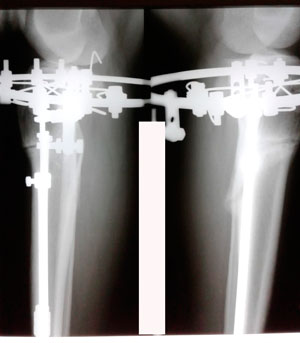

На фиксации

image-26-02-20-08-14-4.jpg

image-26-02-20-08-14-3.jpg